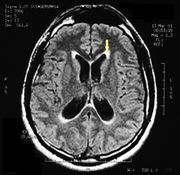

| 21:25, 26 February 2023 | Pineal cavernoma pre surgery 2.jpeg (file) |  |

161 KB | 1 | |